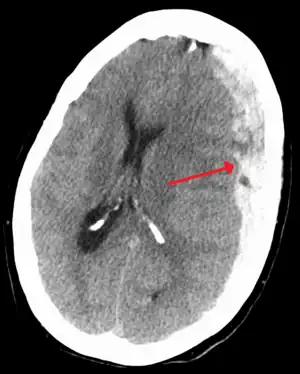

Chronic subdural after treatment with burr holes

On a CT scan, subdural hematomas are classically crescent-shaped, with a concave surface away from the skull. However, they can have a convex appearance, especially in the early stages of bleeding. This may cause difficulty in distinguishing between subdural and epidural hemorrhages. A more reliable indicator of subdural hemorrhage is its involvement of a larger portion of the cerebral hemisphere. Subdural blood can also be seen as a layering density along the tentorium cerebelli. This can be a chronic, stable process, since the feeding system is low-pressure. In such cases, subtle signs of bleeding—such as effacement of sulci or medial displacement of the junction between gray matter and white matter—may be apparent.

Treatment of a subdural hematoma depends on its size and rate of growth. Some small subdural hematomas can be managed by careful monitoring as the blood clot is eventually resorbed naturally. Others can be treated by inserting a small catheter through a hole drilled through the skull and sucking out the hematoma.

Large or symptomatic hematomas require a craniotomy. A surgeon opens the skull and then the dura mater; removes the clot with suction or irrigation; and identifies and controls sites of bleeding.[28][29] The injured vessels must be repaired. Postoperative complications can include increased intracranial pressure, brain edema, new or recurrent bleeding, infection, and seizures. In patients with a chronic subdural hematoma but no history of seizures, it is unclear whether anticonvulsants are harmful or beneficial.[30]